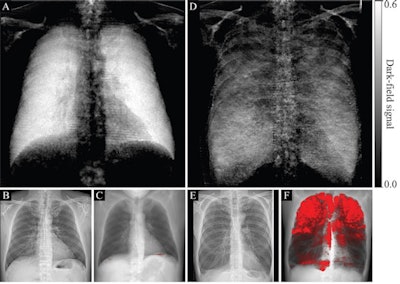

German researchers tested a prototype they developed to see whether dark-field x-ray signals can help visualize as well as quantify pulmonary emphysema compared to images in healthy participants. They found the dark-field chest x-ray technique correlated significantly with conventional CT measures for mild, moderate, and advanced destructive emphysema.

The researchers found that locations of focal signal intensity loss on dark-field images corresponded well with emphysematous areas found on CT images. The quantitative analysis showed the dark-field coefficient was negatively correlated with the CT-based emphysema index for all participants (r = -0.54; p < 0.001), the group wrote.

"Both the CT-based visual emphysema grades and the quantitative emphysema index in CT scans showed results consistent with the quantitative dark-field coefficient, suggesting that quantitative dark-field imaging may be a useful tool in the assessment of pulmonary emphysema," the authors wrote.